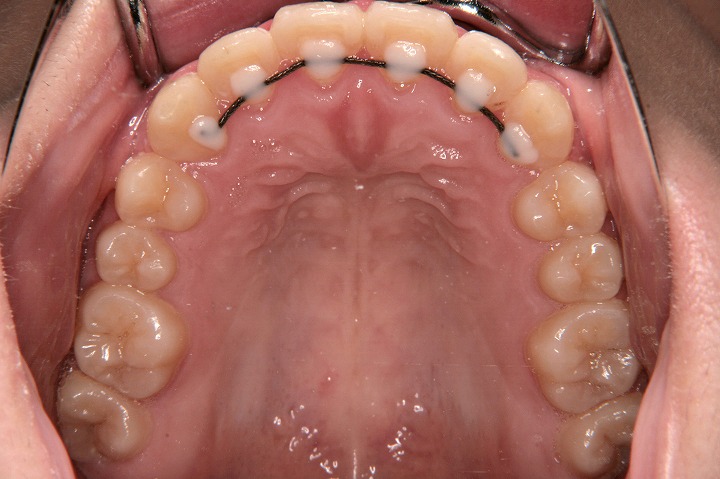

歯のデコボコを主訴に来院された小学校3年生の患者さんです。リンガルアーチを用いて上顎前歯の配列から開始し、バイヘリックスで下顎の側方拡大も行いました。その後、その空隙を利用して、非抜歯でエッジワイズ装置を用いて配列を行っております。拡大処置1年半、その後定期観察を経て、後期約2年半で治療いたしております。